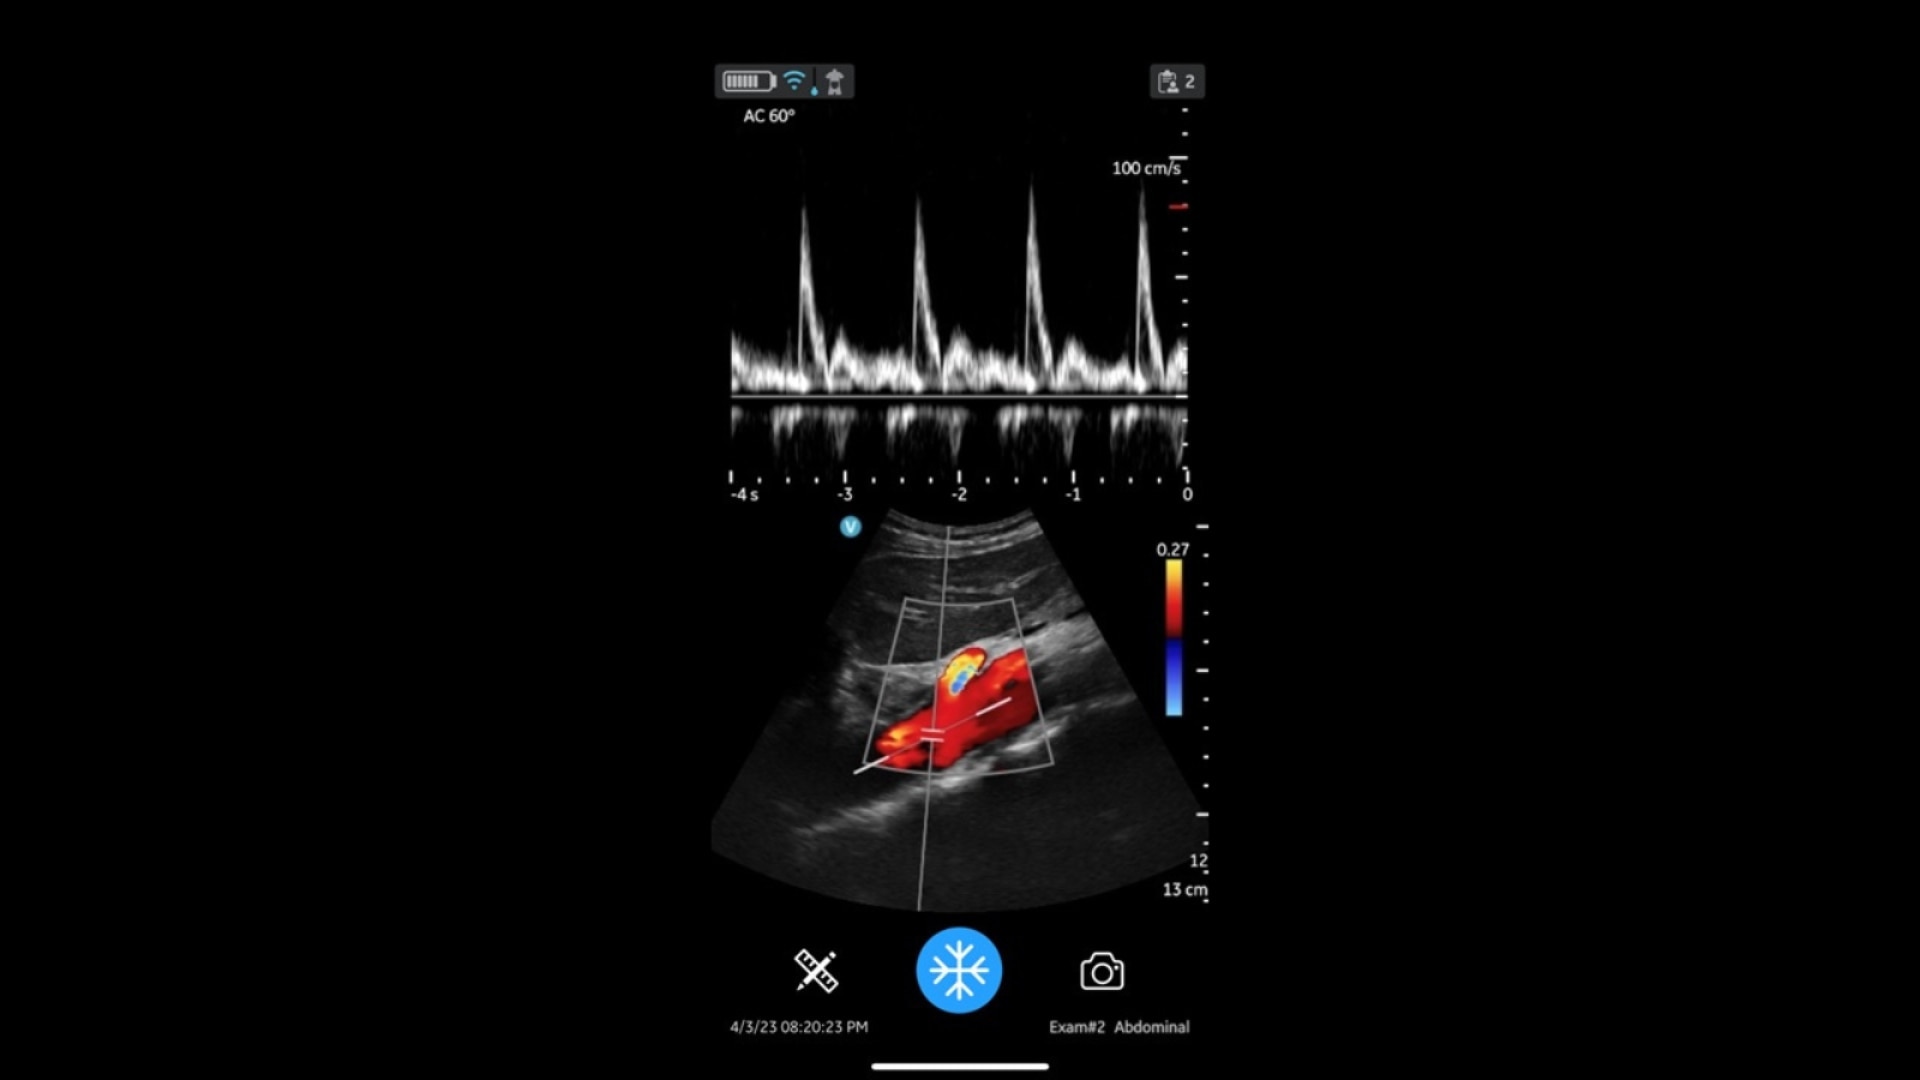

AI supported

Available AI features assist in clinical image interpretation and can help enhance diagnostic accuracy.

Immediate assessments

Immediate imaging can lead to faster treatment decisions, improving patient outcomes.